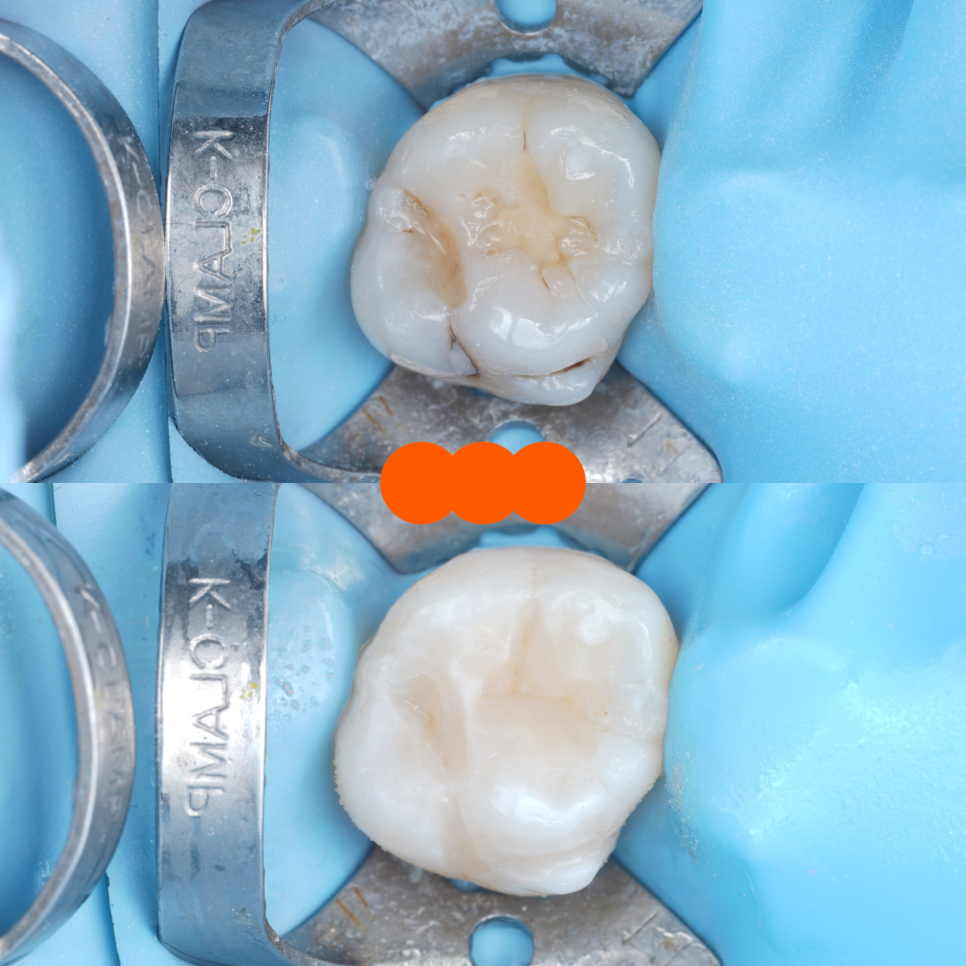

기존 재료 아래에 하얗게 굳은 재료(ZPC로 추정)가 두껍게 깔려 있었어요.

촬영일 : 251110

쉽게 말하면 레진이 치아에 붙어 있는 게 아니라 ‘시멘트 같은 재료’ 위에 붙어 있는 구조였던 거죠.

이 구조는 아무리 레진을 잘해도

깨지고 빠질 수밖에 없어요...

레진은 치아에 직접 붙어야 튼튼해지거든요.

그래서 저희는 기존에 했던 재료를 최대한 깨끗하게 걷어내고 바닥을 다시 정리했어요.

그리고 그 치아에 직접 레진이 단단하게 붙도록 구조를 다시 만들고 씹는 힘이 골고루 분산되도록 모양도 재설계했어요.

#46 / 촬영일 : 251110